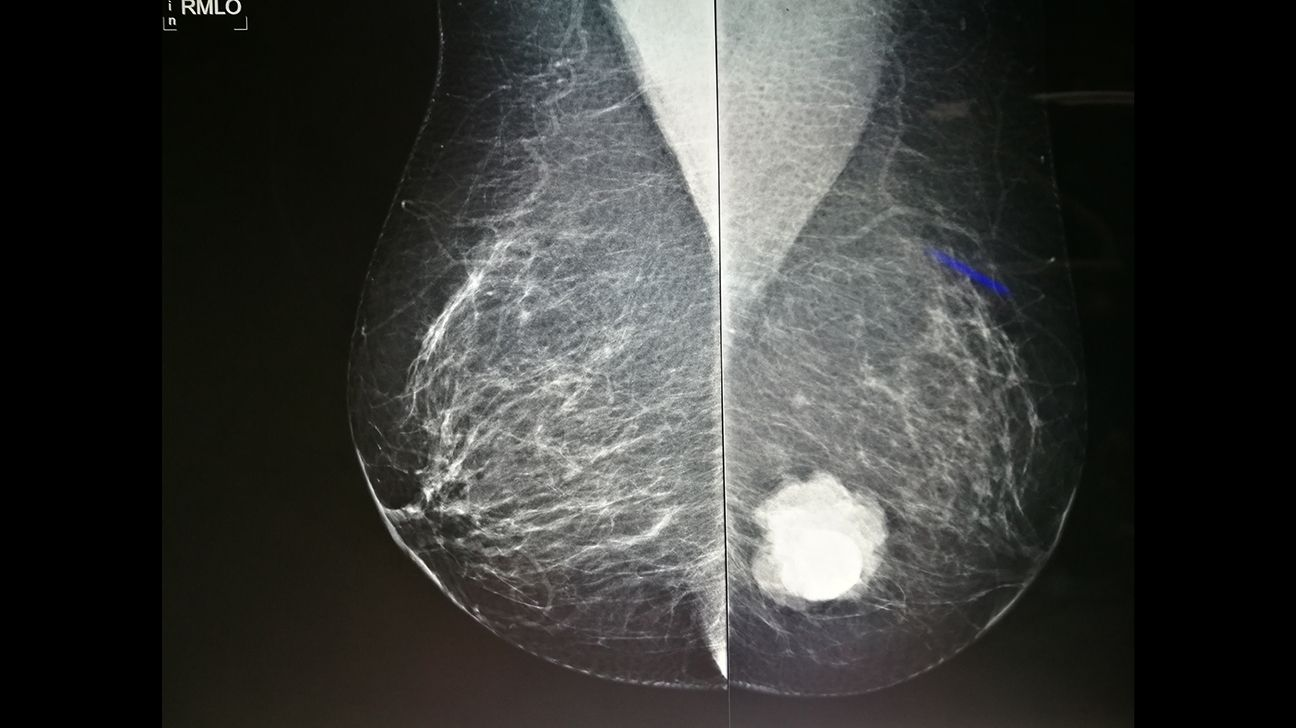

乳腺影像报告看不懂?教你读懂"乳房健康晴雨表"!

乳腺健康,每个女性都应该关注!定期筛查 + 健康生活方式,是守护乳房、远离乳腺癌的"双保险"!